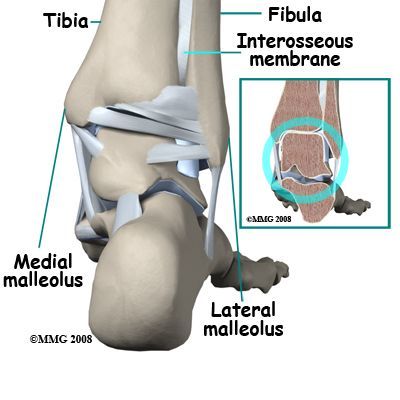

The ankle joint and the associated ligaments can be visualised as a ring in the coronal plane.

Identify and describe the borders of this ring

In light of the ankle ring, discuss what is meant by stable and unstable ankle fractures